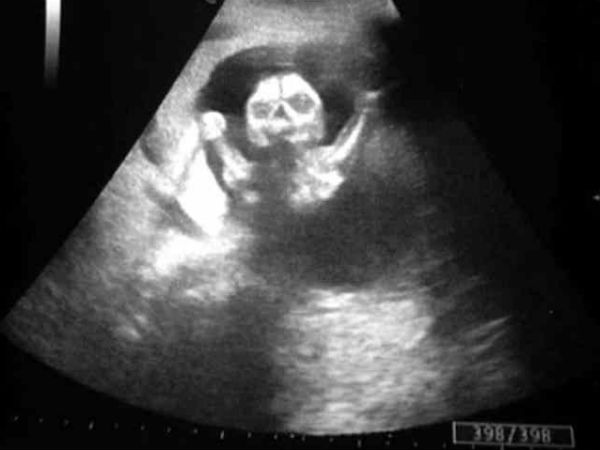

ಚಿತ್ರ#5 ಈ ಮಗುವಿನ ಅಸ್ಥಿಪಂಜರ ಕಾಣಿಸುತ್ತಿದೆ

ಈ ಚಿತ್ರ ನೋಡಲಿಕ್ಕೆ ಮಗುವಿನಂತೆಯೇ ಇದ್ದರೂ ಇದು ನಿಜವಾದ ಚಿತ್ರವೇ ಅನ್ನುವುದು ಮಾತ್ರ ಅನುಮಾನ. ನಿಮಗೇನೆನಿಸುತ್ತದೆ? ಹುಟ್ಟದ ಮಗುವಿಗೆ ಹಲ್ಲೇ ಇರುವುದಿಲ್ಲ. ಹಾಗಾಗಿ ಇದು ನಿಜವೋ ಅಲ್ಲವೋ ಎಂಬ ನಿಷ್ಕರ್ಷೆಗೂ ಮುನ್ನ ಮುಂದಿನ ಚಿತ್ರಗಳನ್ನು ನೋಡೋಣ...